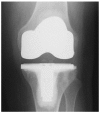

Background: Severe arthritis of the knee is a disabling condition, with over 50,000 knee replacements performed each year in the UK. Isolated patellofemoral joint arthritis occurs in over 10% of these patients with the treatment options being patellofemoral arthroplasty or total knee arthroplasty. Whilst many surgeons believe total knee arthroplasty is the 'gold standard' treatment for severe knee arthritis, patellofemoral arthroplasty has certain potential advantages. Primarily, because this operation allows the patient to keep the majority of their own knee joint; preserving bone-stock and the patients' own ligaments. Patellofemoral arthroplasty has also been recognised as a less 'invasive' operation than primary total knee arthroplasty, facilitating a more rapid recovery. There are currently no published results of randomised clinical trials comparing the two arthroplasty techniques. The primary objective of the current study is to assess whether there is a difference in functional knee scores and quality of life outcome assessments at one year post-operation between patellofemoral arthroplasty and total knee arthroplasty. The secondary objective is to assess the complication rates for both procedures.

Methods/design: Patients who are deemed suitable, by an Orthopaedic Consultant, for patellofemoral arthroplasty and medically fit for surgery are eligible to take part in this trial. The consenting patients will be randomised in a 1:1 allocation to a total knee or patellofemoral arthroplasty. The randomisation sequence will be computer generated and administered by a central independent randomisation service. Following consent, all participants will have their knee function, quality of life and physical activity level assessed through questionnaires. The assigned surgery will then be performed using the preferred technique and implant of the operating surgeon. The first post-operative assessments will take place at six weeks, followed by further assessments at 3, 6 and 12 months. At each assessment time point all complications will be recorded. In addition, community and social care services usage will be collected using a patient questionnaire at 3, 6 & 12 months. The patients will then be sent an annual postal questionnaire. The questionnaire will ask about any problems, knee pain and function following their knee arthroplasty to monitor long-term function and failure rates.